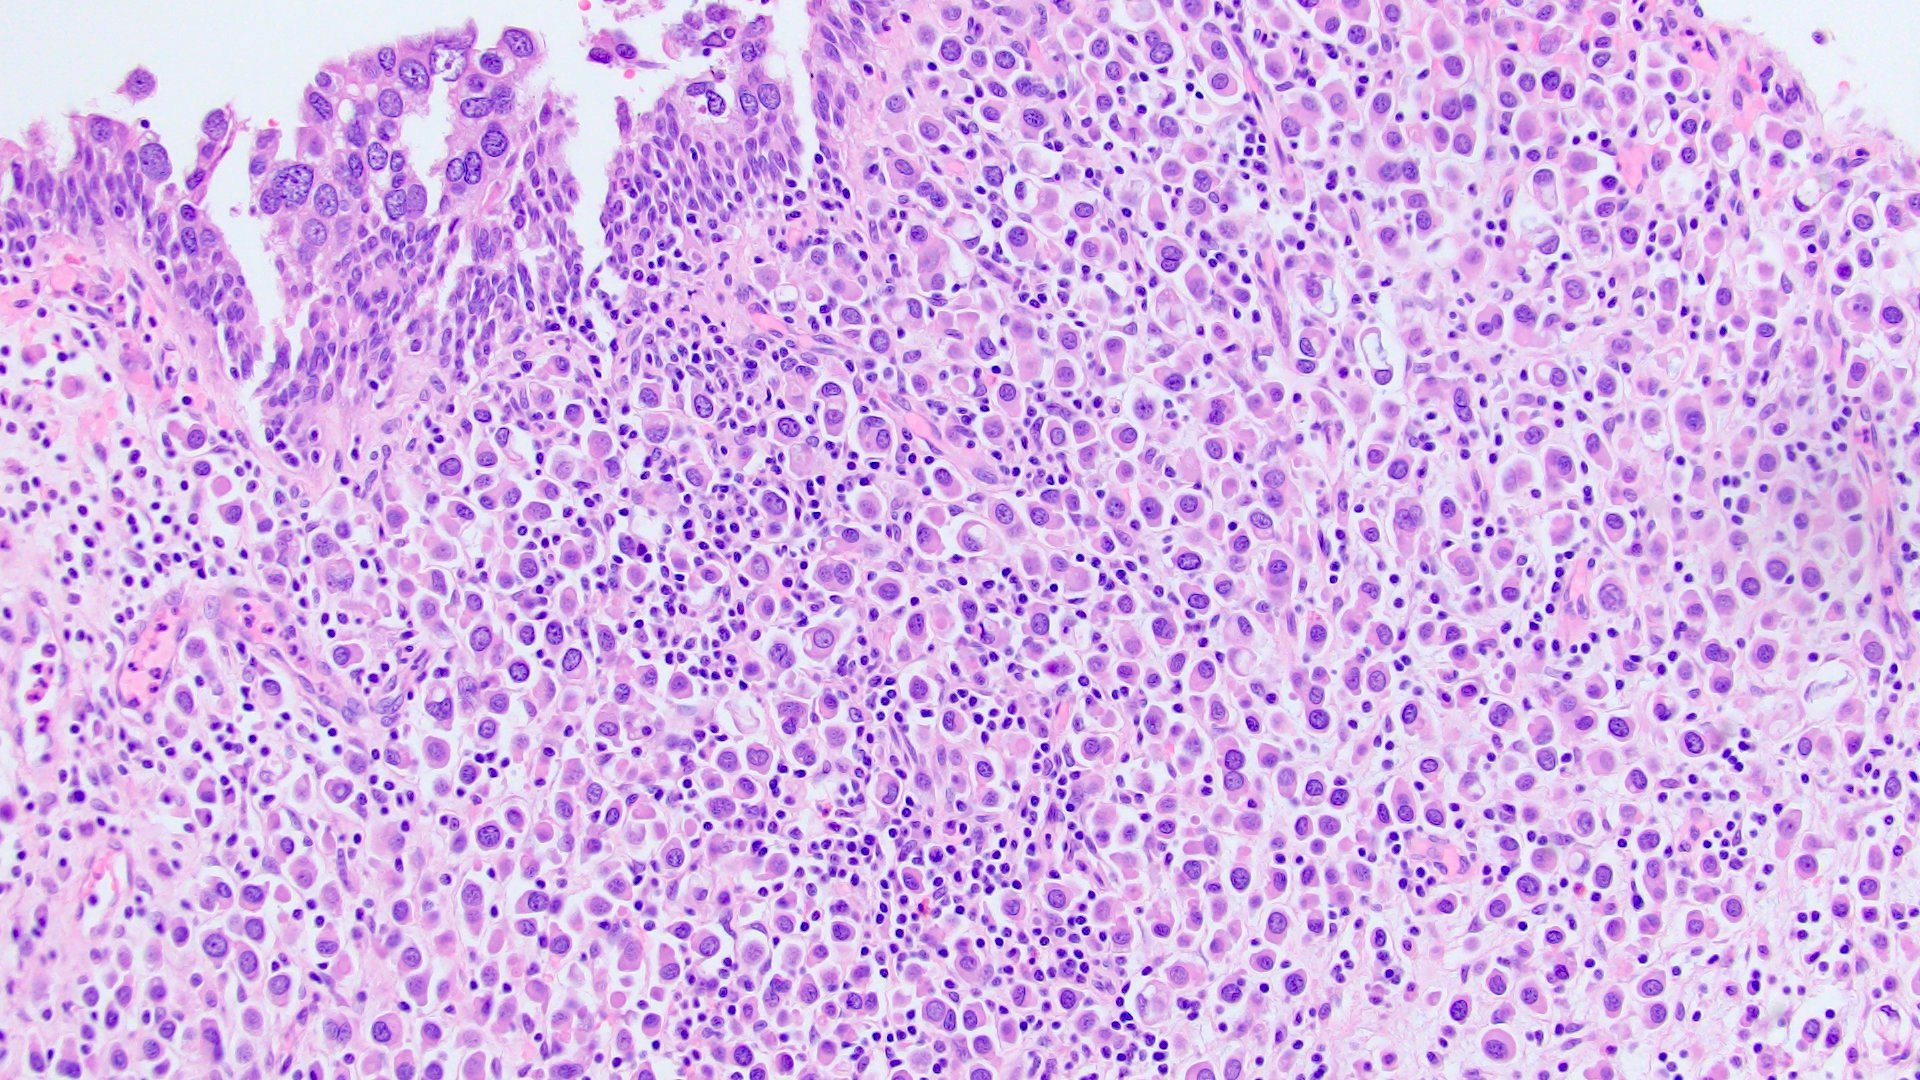

- Discohesive single cells with eccentrically placed nuclei and abundant eosinophilic cytoplasm

- Often deeply infiltrative but with minimal stromal reaction (Eur Urol Focus 2020;6:653)

- Further subclassified into classic, pleomorphic and desmoplastic subtypes:

- Classic: signet ring-like morphology, singly scattered and discohesive in loose aggregates forming cords (Hum Pathol 2019;90:27)

- Pleomorphic: similar to classic but with pleomorphic nuclei and more atypia; can be rhabdoid and bizarre appearing (Hum Pathol 2019;90:27)

- Desmoplastic: plasmacytoid neoplastic cells with a surrounding desmoplastic stromal response (Hum Pathol 2019;90:27)

- Associated with sarcomatoid variant in 31% of cases (Hum Pathol 2019;90:27)

- Often mixed with other histologic subtypes; in 1 case series, 53% of PUC had mixed histologic subtypes (Am J Clin Pathol 2017;147:500)

- Despite resemblance to signet ring carcinoma cells, notably lack extracellular mucin, contrasting to signet ring adenocarcinoma (Acta Cytol 1991;35:277, Am J Surg Pathol 1991;15:569)

Microscopic (histologic) images

Contributed by Timothy Isaac Miller, M.D., M.A., Nicole K. Andeen, M.D. and Maria Tretiakova, M.D., Ph.D.

Contributed by Lisa Han, M.D. and Ricardo Lastra, M.D. (Case #510)